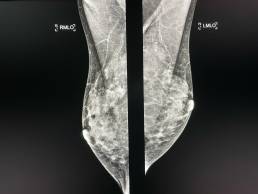

Cas de la semaine (semaine 32, 2021)

Femme de 45 , mammographie de depistage individuelle.

Mammoscreen pointe un surcroît d’opacité en projection axillaire.

Carcinome infiltrant SBRII confirmé.